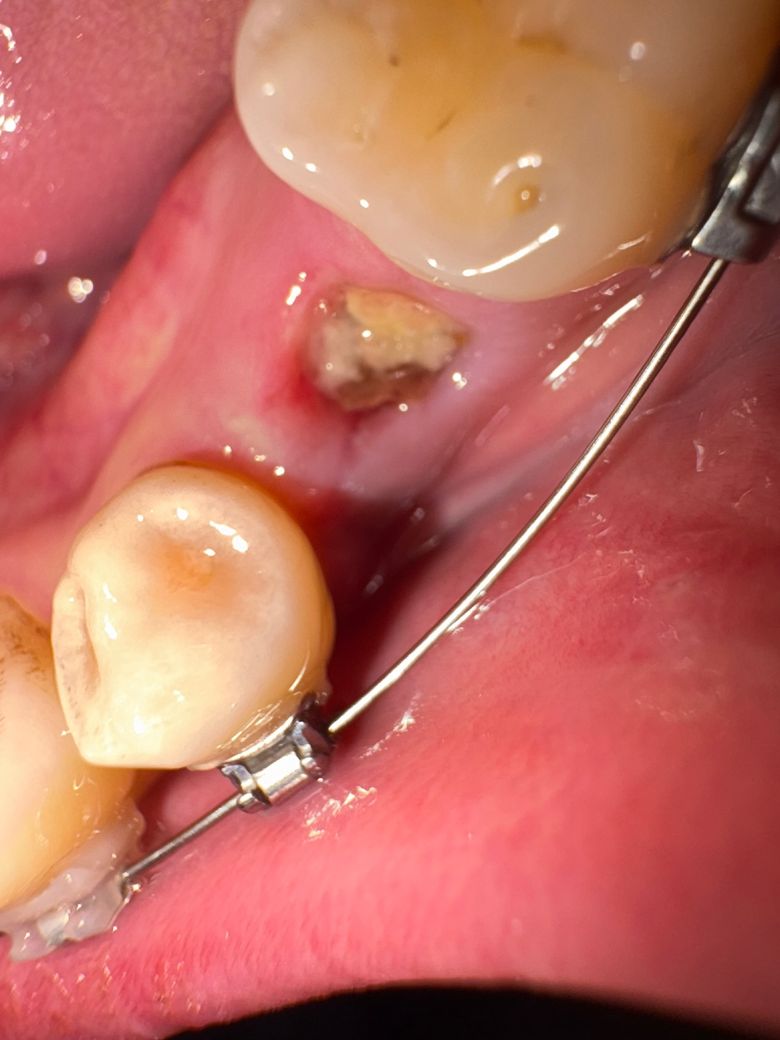

교정 발치 3일차인데 살짝살짝 찌르는 느낌이 있어 걱정이 들어서요.. 이거 드라이소켓인가요?

음식물인거 같긴한데 궁금합니다

-> 단순 이물질 같습니다.

이물질일 것 같습니다 드라이소켓의 양상은 아니고여 이물질 자극가지 않게 부드럽게 잘 빼주어야 치유가 잘 됩니다